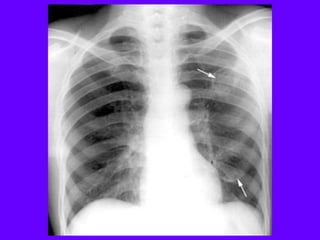

A cavity is > 1cm

in diameter, and its

wall thickness is

more than 3 mm.